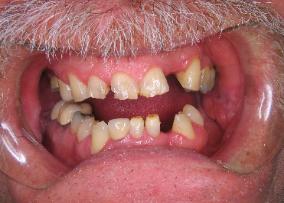

New patients will often come to our office feeling very embarassed, saying things like,

"You've never seen anything this bad before".  Well, we have.  This patient's mouth

was restored with a combination of crowns, bonding, partial denture and bleaching.

Eating is much easier, and he has a very nice smile.